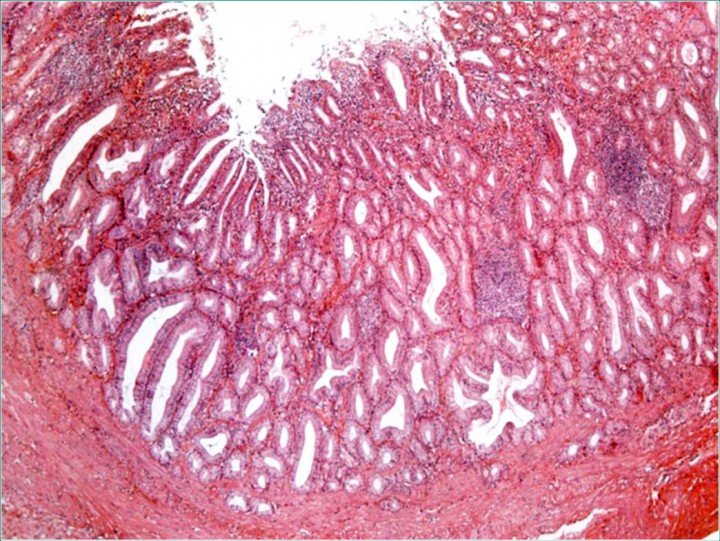

Se remitió la vesícula biliar para su estudio histopatológico (Fig. 3), que evidenció un engrosamiento de su mucosa con pérdida del epitelio superficial y proliferación de células epiteliales a modo de criptas, entre fascículos de fibras musculares lisas con un fuerte infiltrado de células plasmáticas y algunos neutrófilos. Se observaba también una extensa proliferación de tejido de granulación, áreas de necrosis y hemorragias focales con presencia de un pigmento de coloración amarillenta e hipertrofia de la túnica muscular. La serosa de la vesícula biliar presentaba un infiltrado moderado de la misma naturaleza que la mucosa, encontrándose muy vascularizada. El diagnóstico histopatológico era de colecistitis hiperplásica crónica.

<p>Estudio histopatológico. Se evidencia un engrosamiento de la mucosa de la vesícula biliar con pérdida focal del epitelio superficial y proliferación de glándulas tubulares en la lámina propia con agregados foliculares linfoides. La túnica muscular estaba hipertrofiada y se observó fibrosis severa de la serosa con un infiltrado moderado, similar a la mucosa. Hematoxilina-Eosina, x50.</p>

Estudio histopatológico. Se evidencia un engrosamiento de la mucosa de la vesícula biliar con pérdida focal del epitelio superficial y proliferación de glándulas tubulares en la lámina propia con agregados foliculares linfoides. La túnica muscular estaba hipertrofiada y se observó fibrosis severa de la serosa con un infiltrado moderado, similar a la mucosa. Hematoxilina-Eosina, x50.